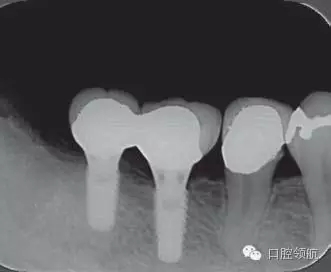

修復(fù)體安裝后的2003年1月復(fù)診時(shí)的X線片上,沒有發(fā)現(xiàn)種植體頸部有骨吸收現(xiàn)象,情況良好(圖2)。但是,2003年8月,因混合陶瓷樹脂部分修復(fù)體的破損而進(jìn)行再制作時(shí),發(fā)現(xiàn)有輕度的咬合疼痛以及舌側(cè)頸部的牙齦有輕壓痛??趦?nèi)沒有觀察到該部位的牙齦紅腫。X線片可以觀察到(左下第6顆牙) 的種植體頸部有達(dá)到第4螺紋的骨吸收現(xiàn)象(圖3)。

圖2 沒有發(fā)現(xiàn)種植體頸部的骨吸收(2003年1月)